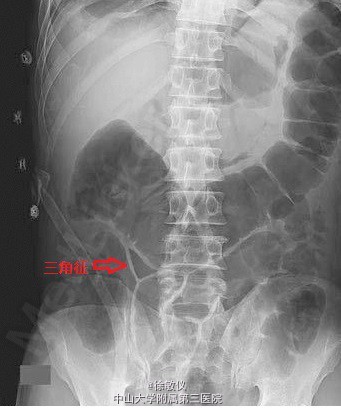

56岁男性,因腹泻及上腹钝痛3天就诊。体检发现腹部弥漫性压痛及反跳痛,肠鸣音消失。腹平片显示三个相邻肠袢形成一个小的含气区域,符合腹腔内游离气体的表现(三角征)。术中发现胃溃疡穿孔且合并两个腹腔脓肿。